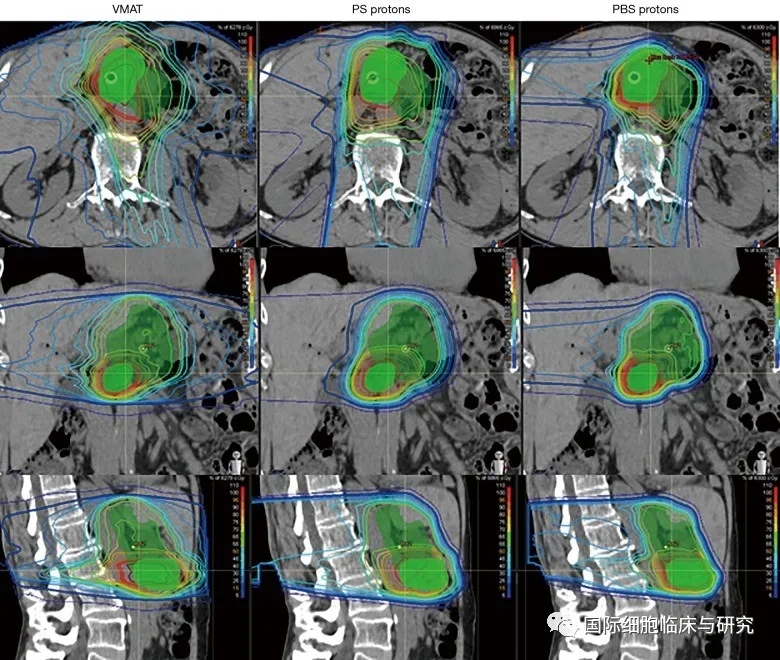

图中所示为容积旋转调强放疗(VMAT,左)、质子同步加速器(PS,中)及笔形束质子疗法(PBS,右)治疗的照射区域对比。绿色色块所示范围为肿瘤及转移淋巴结的区域范围;细线所示范围从红色至蓝色,放射剂量从高至低。

我们可以看出,在保持病灶部位所受放射剂量一致的情况下,两种质子治疗方案对于病灶以外的正常组织造成的放射剂量均低于光子方案。且质子治疗方案最大的特点是,质子束在击中病灶区域后剂量迅速降低至零;光子束却会一直穿过人体,剂量缓慢衰减,至穿出人体。